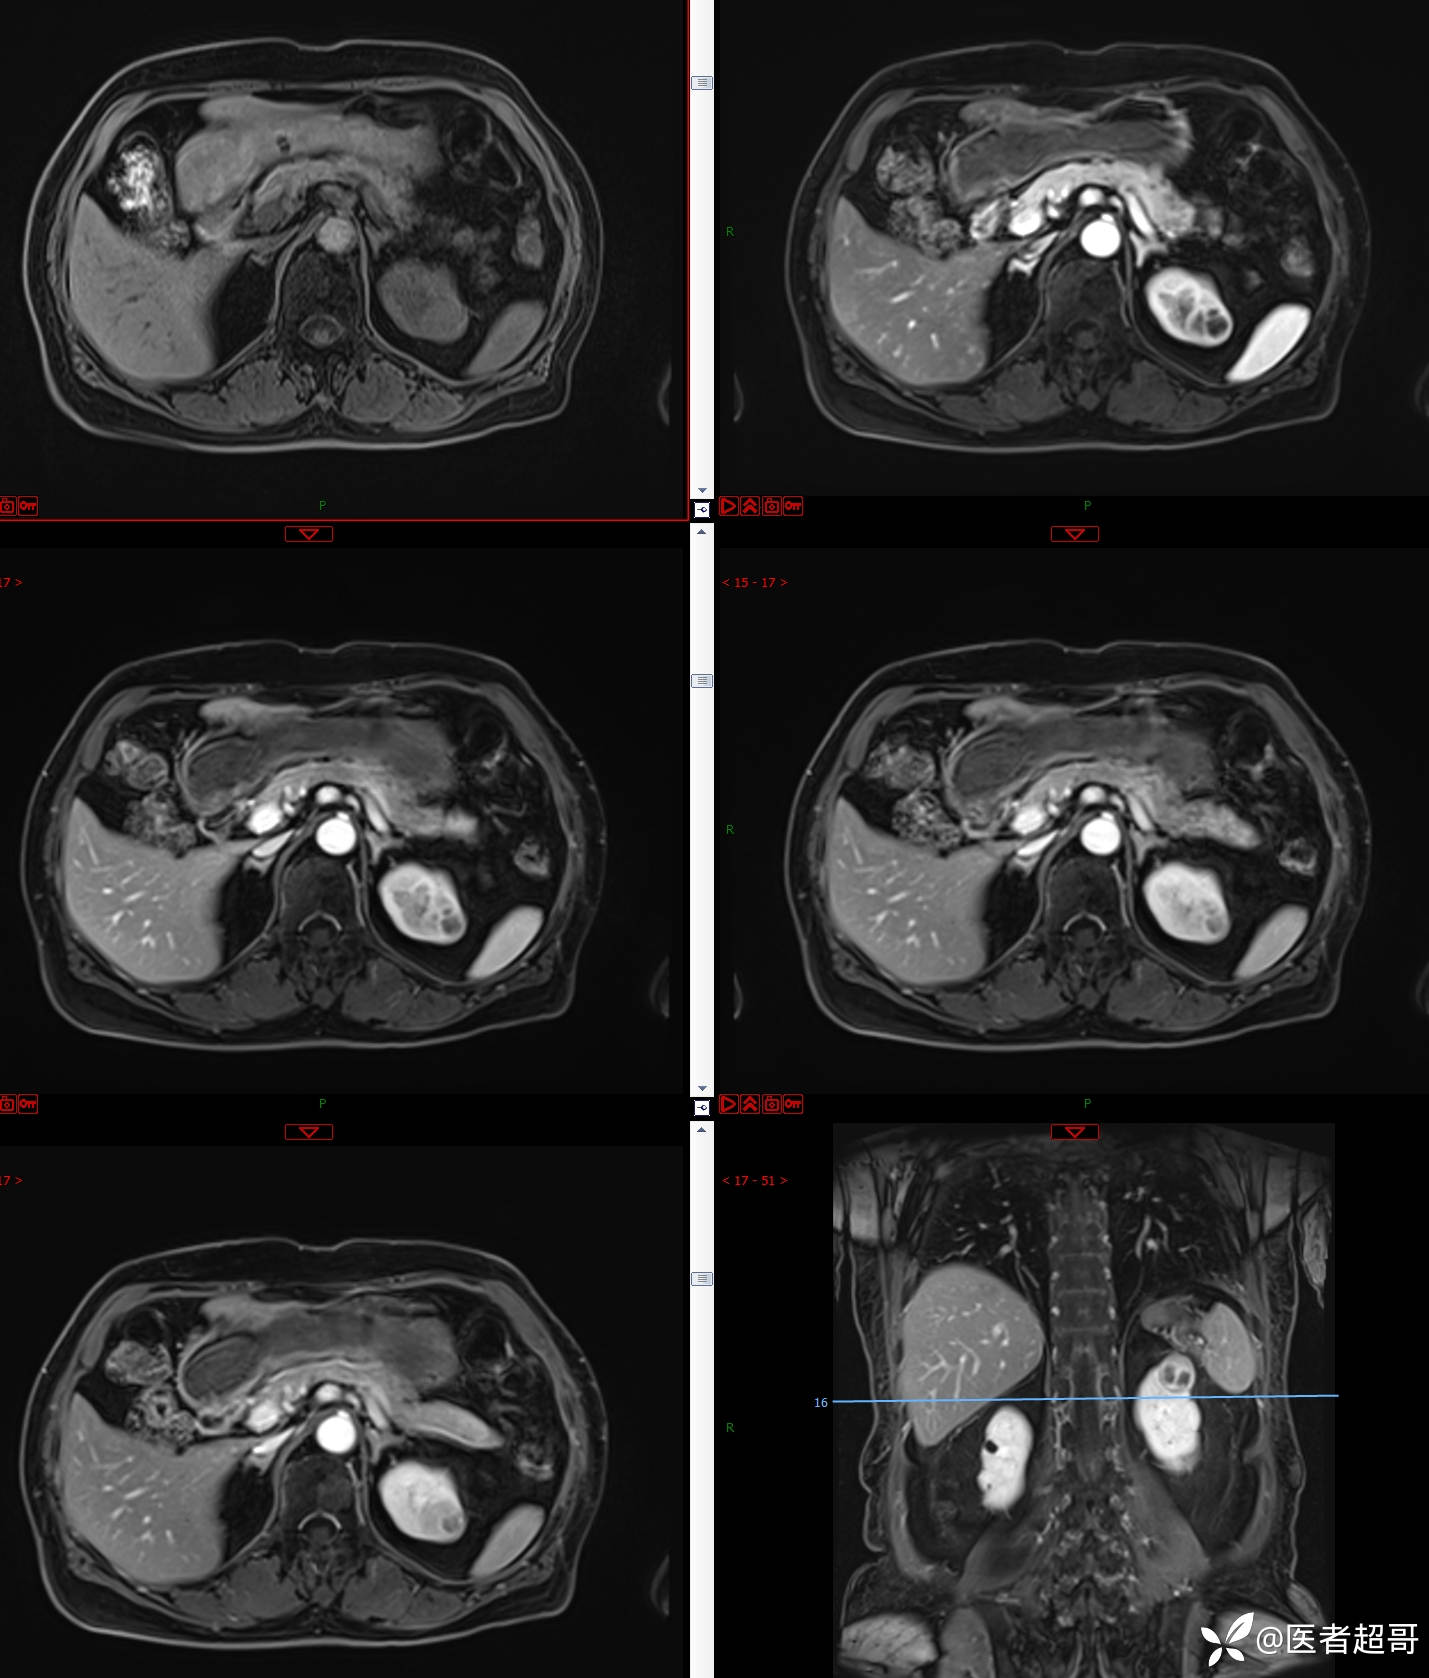

左肾占位2个月就诊,有病理,请分析!

主 诉:查体发现左肾占位2月。

现病史:患者自述2月前于镇中心卫生院行腹部超声发现:左肾实性占位。患者无尿频尿急尿痛,无发热寒战,无恶心呕吐。未行特殊治疗。现患者为求进一步诊治,就诊我院,门诊以“肾肿物”为诊断收入院,患者自发病以来,神志清,精神可,饮食可,睡眠一般,大便正常,体重未见明显改变。